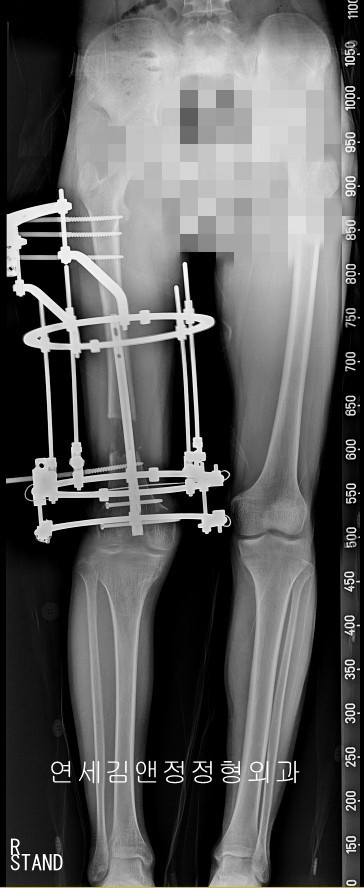

종아리 속성연장 시 착용하는 외고정은 원통형 일리자로프와 일자형 모노픽세이터를 사용할 수 있지만, 원통형 일리자로프가 더 많이 사용되는데 이는 체중부하와 정렬 교정에 유리하기 때문이다. 즉 원통형 일리자로프 외고정을 착용하는 약 2-3개월의 기간 동안은 불편하지만, 체중부하가 가능하기 때문에 서거나 걷거나 운동이 가능하고, 이 때문에 일상생활로 빨리 돌아갈 수 있는 재활에 장점을 갖는다.

내고정 삽입 후 일리자로프 외고정장치

내고정 삽입은 슬개건을 통해서 삽입하며, 삽입가능한 내고정의 길이와 두께는 환자의 뼈길이와 골수내강의 공간의 넓이에 따라 결정된다. 두껍고 긴 내고정이 유리한점이 있지만, 지나친 확공은 골수내강의 재생환경을 손상시킬수 있으므로 주치의의 경험에 따른 선호하는 길이와 두께를 선택하게 된다.

내고정 근위부 잠김나사만 삽입, 원위부 잠김나사는 연장 종료후 2차 수술시 외고정 제거직전에 삽입한다. 내고정 삽입 후 근위부와 원위부 고정나사 중 근위부만 삽입하여 내고정을 따라서 골연장이 되며, 키 연장과 골연장이 종료될 시점에 정렬 교정 후 원위부 잠김나사를 삽입하여 키연장 및 교정 상태를 고정후 일리자로프 외고정을 제거한다.